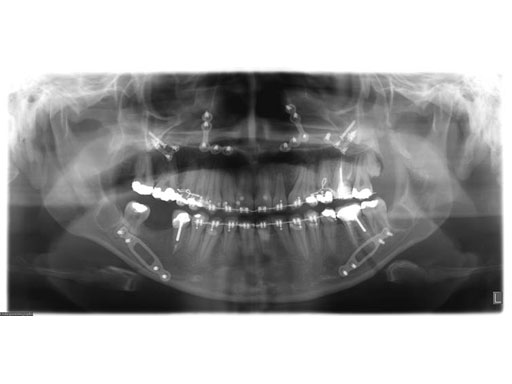

Lefort I maxillary osteotomy, bilateral sagittal osteotomies, and a genioplasty, all fixed with matrix orthognathic system used in a 19-year-old female with significant skeletofacial deformity including maxillary hypoplasia, mandibular excess, and laterognathia.

Fig 2a-c Postoperative images.